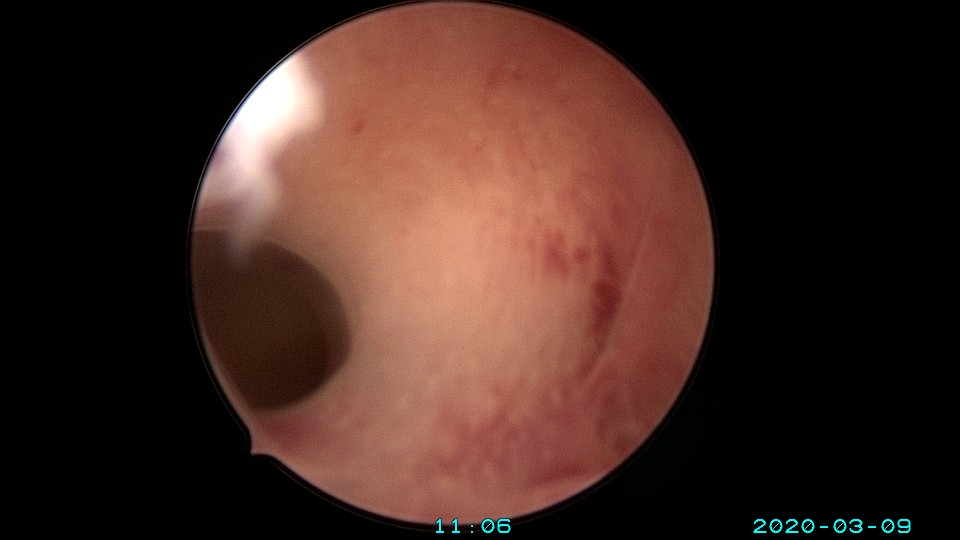

患者36岁,G3P0,自然流产3次,发现宫腔粘连3个月。2020年3月宫腔镜探查,子宫前倾后屈位,宫深8.5cm,宫颈管粘连狭窄,扩宫进入宫腔,见宫腔中下段两侧壁粘连,剪刀及双极电切分粘,宫腔形态恢复正常,双侧输卵管开口显露。2020年4月宫腔镜二探取球囊,宫腔形态正常,双侧输卵管开口可见。2021年6月自然妊娠,2022年2月足月剖宫产分娩。现42岁,G4P1。